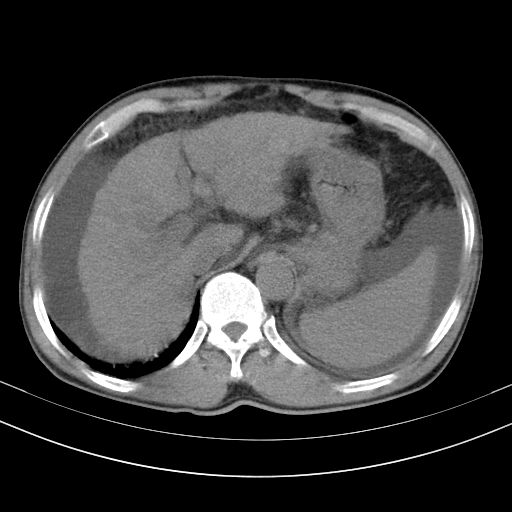

以下是引用随光逐影在2010-2-28 10:23:00的发言:[br]1)考虑肝癌;建议行ct增强扫描检查。2)肝硬化,脾大,腹水。3)慢性胆囊炎。